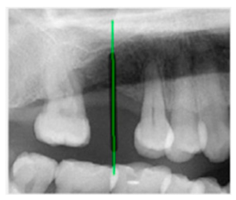

The angle bisector of the two auxiliary lines was then calculated using the angle bisector formula shown in (8), where (, , ) and (, , ) represent the coefficients of the two lines. The resulting internal angle bisector defines the preliminary implant pathway orientation derived by this framework. This bisector represents the most stable implant pathway orientation direction, ensuring that the implant avoids adjacent teeth and critical anatomical structures while maximizing bone–implant contact area. Such orientation enhances osseointegration stability and prevents complications from improper angulation, such as malocclusion or uneven stress distribution. The visualization of this process and the algorithmic design are presented in Figure 8. Finally, the auxiliary pathway generated by the algorithm was compared and overlapped with the implant pathway orientation annotated by dentists on the images to evaluate the predictive capability and accuracy of the model. The overlap results serve as a basis for further model optimization and provide valuable reference information for clinical application.

Figure 8.

Auxiliary lines are derived from adjacent teeth, the blue and yellow line is the result of implant pathway orientation visualization algorithm, and the green is the best implant pathway orientation.

3.3. Comparison with Clinical Ground Truth and AI-Assisted Framework

This subsection presents a comparison between the dentist-defined clinical gold standard and the predictions generated by our AI-assisted framework to evaluate the reliability of implant pathway orientation. The result is shown in Table 10, the preserved DPR validation set was used for verification, and the AI-assisted framework results were overlaid onto the original DPR images to provide a clear visualization. The AI-assisted framework pathways (green lines) were highly consistent with the dentists’ ground-truth annotations (black lines). Quantitatively, the mean squared error (MSE) between the predicted implant direction and the dentists’ planned results was only 1.537° across multiple test images. This minimal deviation validates the proposed system’s technical feasibility. It highlights its clinical potential to provide accurate and stable guidance for implant placement, thereby reducing the risk of misalignment and supporting efficient preoperative orientation.